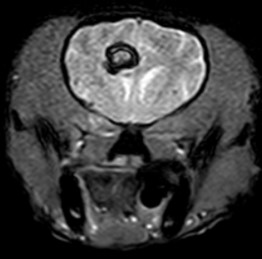

뇌수두중 -

후두골이형성,키아리 기형 -

척수공동증 -

AAI

- 뇌수두증

- 뇌종양

- 뇌수막염

- 두경접합부 질환

- 디스크 질환

- 척수 질환

자기공명영상촬영 (MRI, Magnetic Resonance Imaging) 자기에너지를 이용하여 영상을 획득하기 때문에 방사선의 발생 없이 사람과 동물 모두에게 보다 안전한 영상 기법입니다.

MRI의 경우 특히 뇌와 척수의 신경계와 같은 연부조직의 영상화에 특화되어 있어 다른 영상 기법보다 뛰어난 해상도를 나타냅니다.

건국대학교 영상진단의학과에서는 1.5 Tesla의 최신 자기공명영상촬영장치를 통해 높은 수준의 해상도를 제공하고 추가적으로 환자에게 맞는 다양한 검사 sequence가 가능하여 보다 정밀한 진단을 위해 노력하고 있습니다.